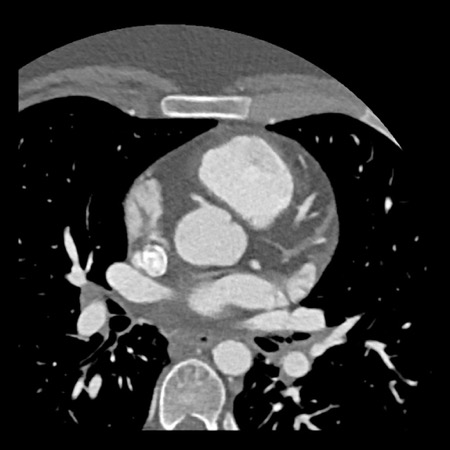

case 1 – CAD-RADS 2/P1

First, scroll through the scan.

Not all images are included. Some images without any abnormalities are skipped

from the series.

How would you describe the findings on the coronary CTA?

The findings are:

- Agatston score of

this patient was 14 (P1). Please, also note the calcification of the aortic valve. - Some partially

calcified and calcified plaques are present in the LAD with mild stenosis

(25-49%). - Calcified-plaque in

the LCX causing minimal stenosis (<25%). - Non-calcified

plaque in the distal RCA causing minimal stenosis (<25%). - This patient classifies

as CAD-RADS 2/P1, which means no further workup is needed.